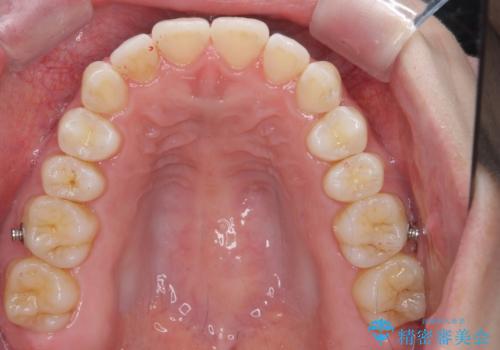

- インビザライン

今回は、下の歯を健康に支障が出ない範囲でわずかに削合し、並べるようにしました。(ディスキングといいます)

前歯のがたつきもしっかり治り、喜んでいただけました。

下の親知らずは虫歯になっていたため矯正前に抜歯しています。